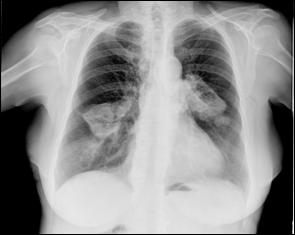

Cele mai multe metasteze la distanta, provocate de tumorile vezicale maligne, sunt localizate in plamani si in oase. Diagnosticul acestora se face prin: radiografii toraco-pulmonare, radiografii osoase sau scintigrame osoase (evidentiaza metastazele osoase cu 9-12 luni mai devreme decat expresia evidenta a acestora pe radiografiile standard).

dreapta Figura 45. Metastaze pulmonare multiple dintr-un carcinom vezical

Figura 4 Radiografie toraco-pulmonara cu metastaze pulmonare multiple

dintr-un carcinom vezical infiltrativ

Figura 47. Radiografie toraco-pulmonara cu metastaze pulmonare multiple dintr-un carcinom vezical infiltrativ.